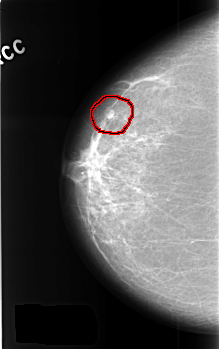

C_0370_1.LEFT_CC

LEFT_CC LINES 4568 PIXELS_PER_LINE 2840 BITS_PER_PIXEL 12 RESOLUTION 50 NON_OVERLAY

FILE: C_0370_1.RIGHT_CC.OVERLAY

TOTAL_ABNORMALITIES 1

ABNORMALITY 1

LESION_TYPE MASS SHAPE LOBULATED MARGINS CIRCUMSCRIBED

ASSESSMENT 3

SUBTLETY 5

PATHOLOGY BENIGN

TOTAL_OUTLINES 1